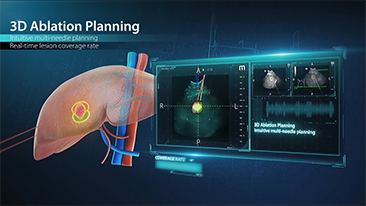

Algemene beeldvorming

Mindray Resona-oplossingen voor algemene beeldvorming helpen clinici bij het realiseren van nauwkeurigere en effici?ntere diagnose- en behandelingsresultaten door middel van sondes voor aparte toepassingen en effici?nte klinische toepassingstools.